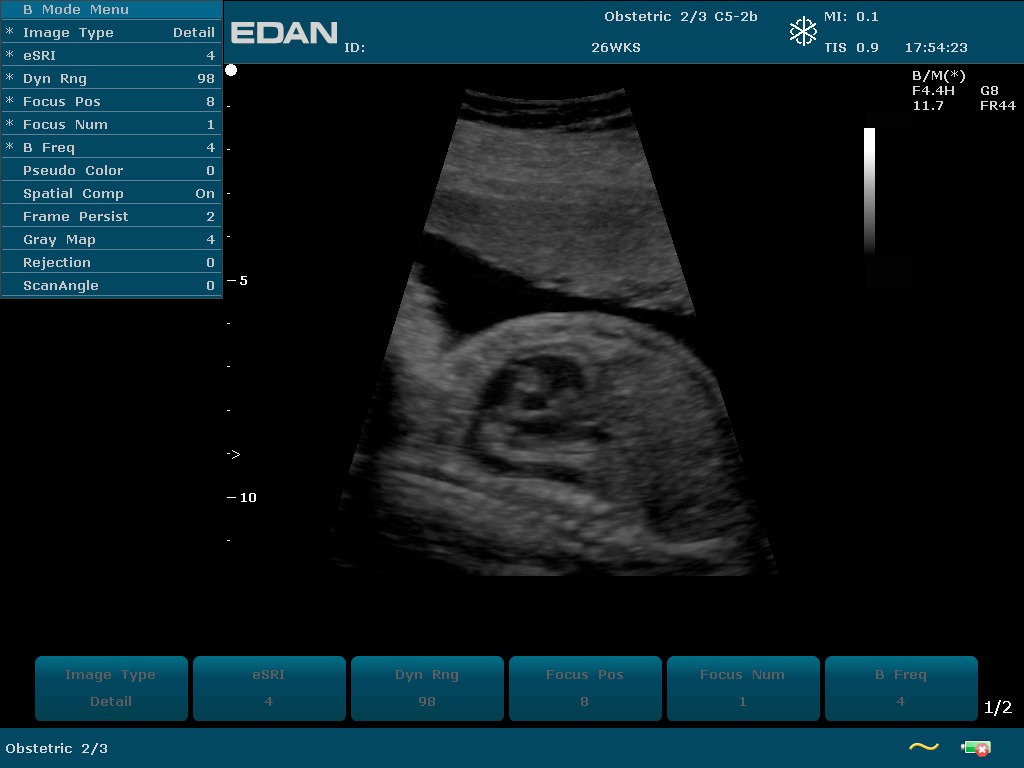

Прибор u2 143 фото